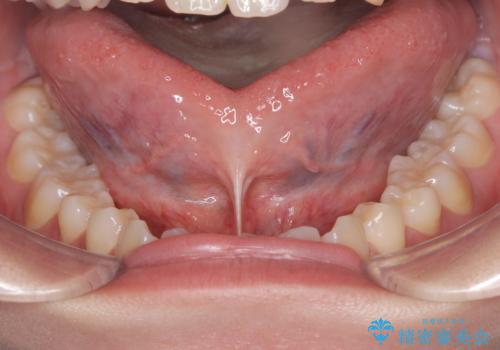

短い舌小帯に舌が引っ張られて舌がハート型になっています。